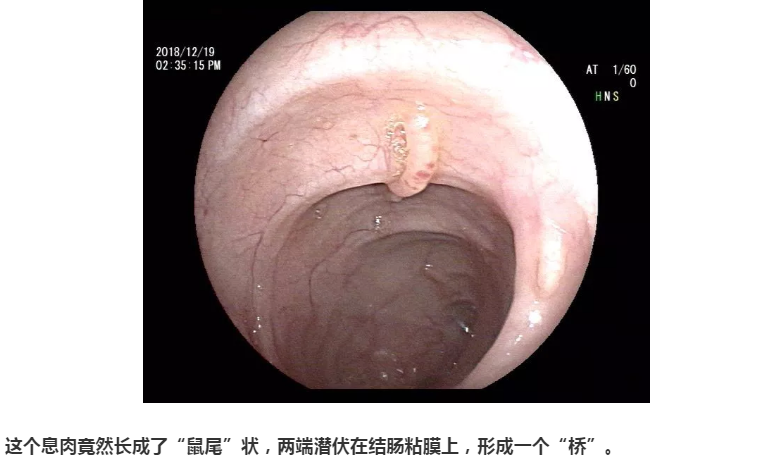

下面就是不一般的了,都是我的宝库,把库存翻出来亮亮相。大千世界,无奇不有。息肉经过进化变异,竟然也长成了各种各样的面孔,医生有时都差点认不出来。甚至都怀疑,你还是曾经的你吗?